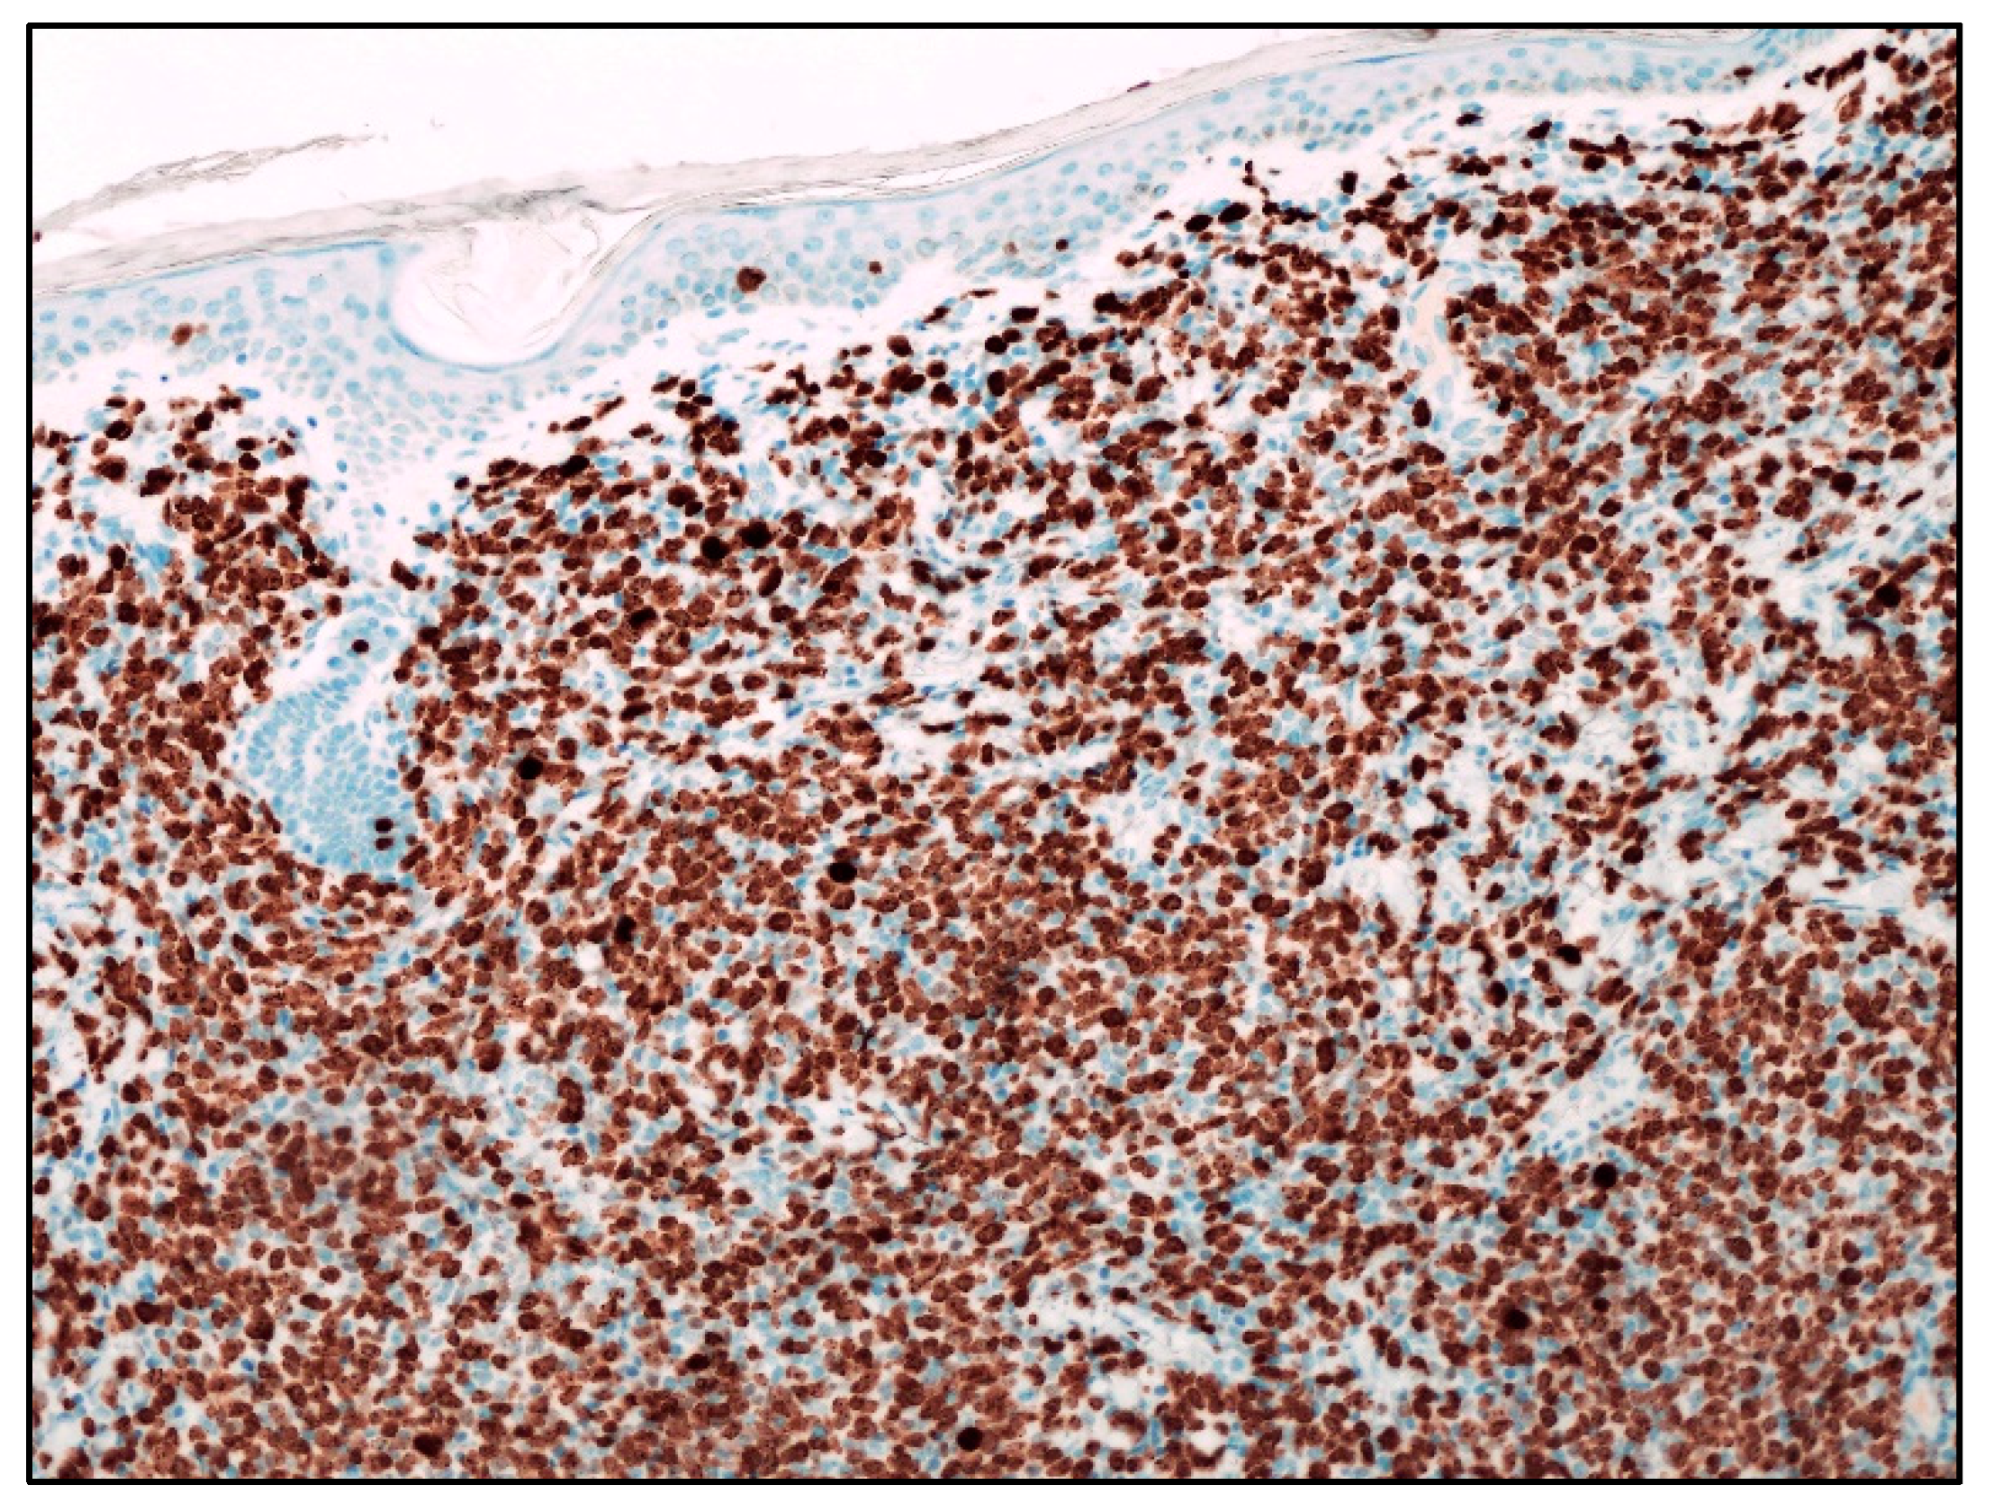

| Blastoid MCL | M:F = 3:1; late sixties | Solitary/multiple papules or nodules; often on extremities. Often previous history of MCL; skin lesions in recurrent and progressive disease | Diffuse dermal and subcutaneous tissue infiltrate; no epidermis and Grenz zone involvement. Monomorphic, medium-sized cells, round/oval nuclei, dispersed chromatin, inconspicuous nucleolus | Mature, naïve B-lymphocytes | CD20+, cyclin D1+, TdT−, CD3−, CD5+ (CD5 loss in 25-28% of blastoid MCL); aberrant expression of CD10, BCL6, CD23; TP53 overexpressed; high Ki67 | Poor. Intensive CT and immunotherapy plus ASCT; recently, anti CD19 CART cells, venetoclax, ibrutinib, acalabrutinib |

| B-LBL | F:M = 2:1 children young adults | Often solitary, firm papule or nodule on head and neck. Skin lesions in 15-33% of B-LBL; skin lesions associated with systemic disease | Dense dermal infiltrate; no epidermis and Grenz zone involvement; uniform, small, medium-sized cells, round/oval/convoluted nuclei, fine chromatin, barely visible nucleoli, scarce basophilic cytoplasm; numerous mitoses | Precursor B- lymphocytes | TdT+, CD34+, CD10+, PAX5+, cCD79alpha+, CD19+, CD22+, high Ki67 | Good prognosis in 70% of cases with B-lineage ALL-type. Multiagent CT. |